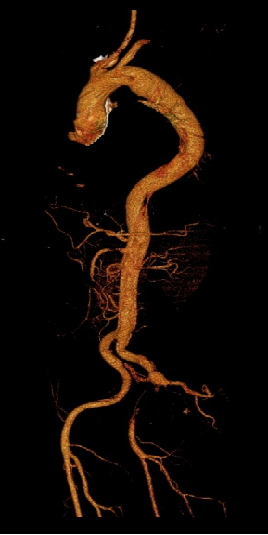

男, 49岁,急性夹层 。2018年11月TEVAR。一月后复查:RTAD 。 2019年1月双开窗。2019年4月2日 复查,结果良好。

▎病例五

男,49岁,急性AD。2019年1月TEVAR,3月RTAD,行全弓置换+支架象鼻。2022 年1月25日术后复查,结果良好。